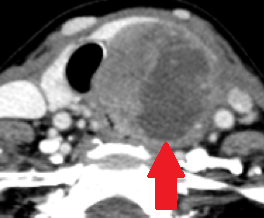

Contrast-enhanced CT demonstrates soft-tissue lesion in left carotid sheath (Courtesy Dr. V. Penopoulos)